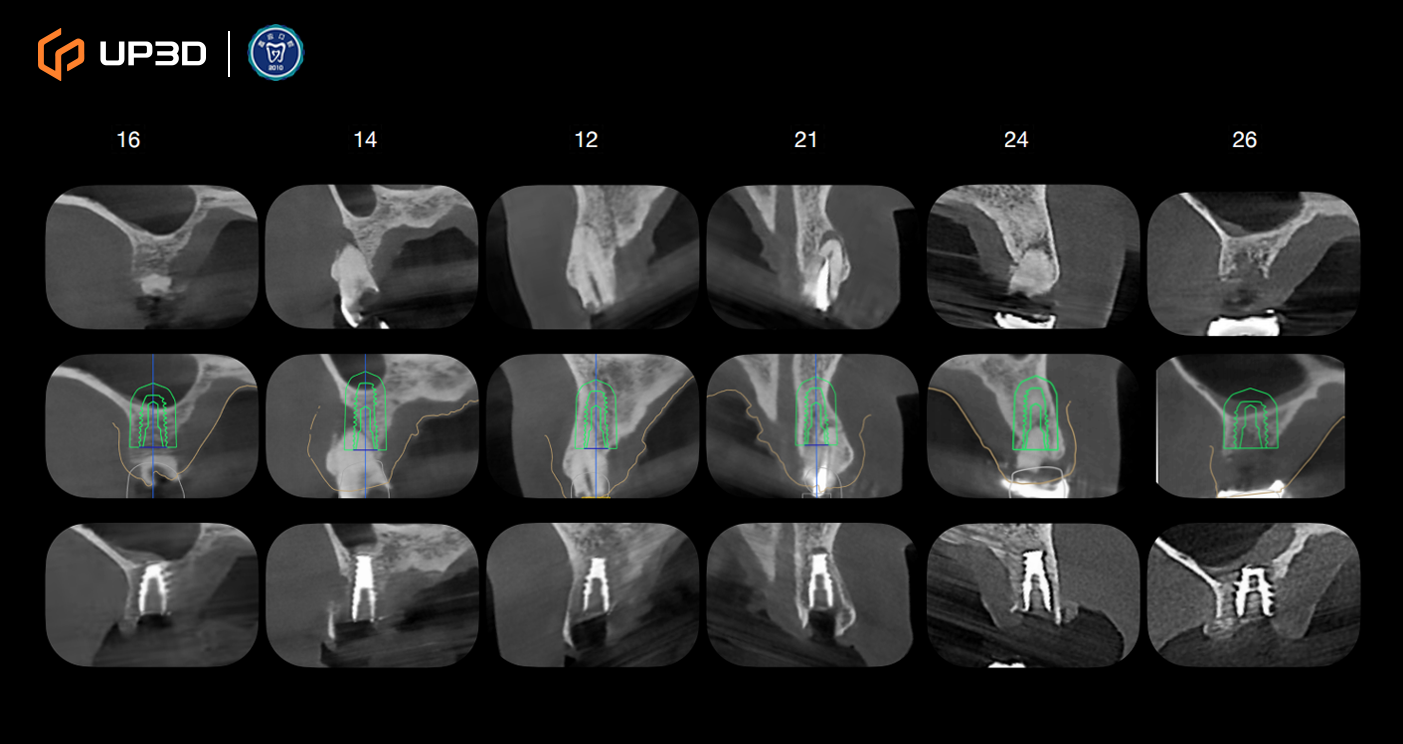

2.3 Radiographic Assessment

A panoramic radiograph and cone-beam computed tomography (CBCT) revealed multiple missing teeth and uneven alveolar ridge resorption, with moderate-to-limited bone volume in selected areas. Based on measurement and analysis, implant placement was planned at sites including 16, 14, 12, 21, 24, 26, 36, 45, and 46 (FDI tooth numbering).

Intraoral scan data were merged with CBCT to complete a 3D implant plan:

Six implants planned in the maxilla and three implants in the mandible

Surgical guide (guided surgery) pathways were planned digitally

Digital tooth setup and guide fabrication supported accurate positioning and a minimally invasive approach

Guided surgery helped improve consistency in implant angulation and depth control, supporting a stable foundation for immediate loading.